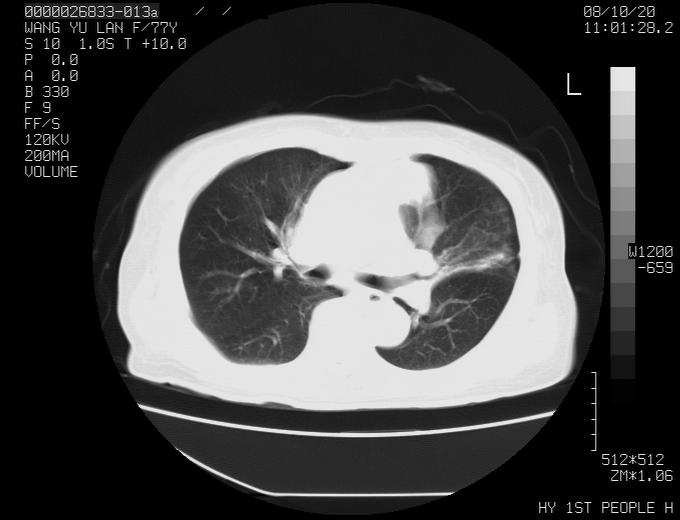

女性,77岁,胸部疼痛半月。左上肺团块影,本人考虑血管畸形,请分析

非常典型的avm(谢谢楼主,收藏了)

左上叶前段多发结节肿块并前段支气管息肉样结节、上叶腋亚段阻塞性肺炎,以结核可能性大。

纵隔有多个淋巴结肿大,提示周围型肺癌并转移可能性大。

1、考虑avm可能性大。2、纵隔有肿大淋巴结,左肺上叶有炎性病变,不排除肺癌并转移可能。